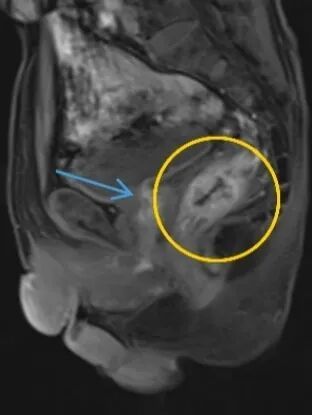

因便血入院时,老张并未意识到问题的严重性。然而,胃镜、肠镜、增强CT……一系列检查后,诊断结果如晴天霹雳:直肠中段腺癌;更令人倒吸一口凉气的是,检查竟意外发现老张的腹主动脉存在孤立性夹层,且直径已超过5厘米。

直肠中段腺癌

主动脉夹层

“这在医学上极其凶险。”主治医师李清华打了个形象的比喻:“把主动脉想象成一根三层结构的水管。正常情况下三层紧密贴合,一旦内层破裂,血液就会像洪水一样钻进夹层,像轮胎鼓包一样越撑越大。老张的血管‘鼓包’已达5厘米,随时可能‘爆胎’,一旦破裂,患者可能在几分钟内因大出血死亡。”